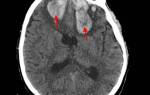

С точностью распознать геморрагический инсульт помогают информативные спиральная (СКТ) или мультиспиральная (МСКТ)

Суть её заключается в послойных рентгеновских снимках головного мозга, на которых кровоизлияние достаточно хорошо видно см. рисунок.

кровоизлияние на КТ головного мозга